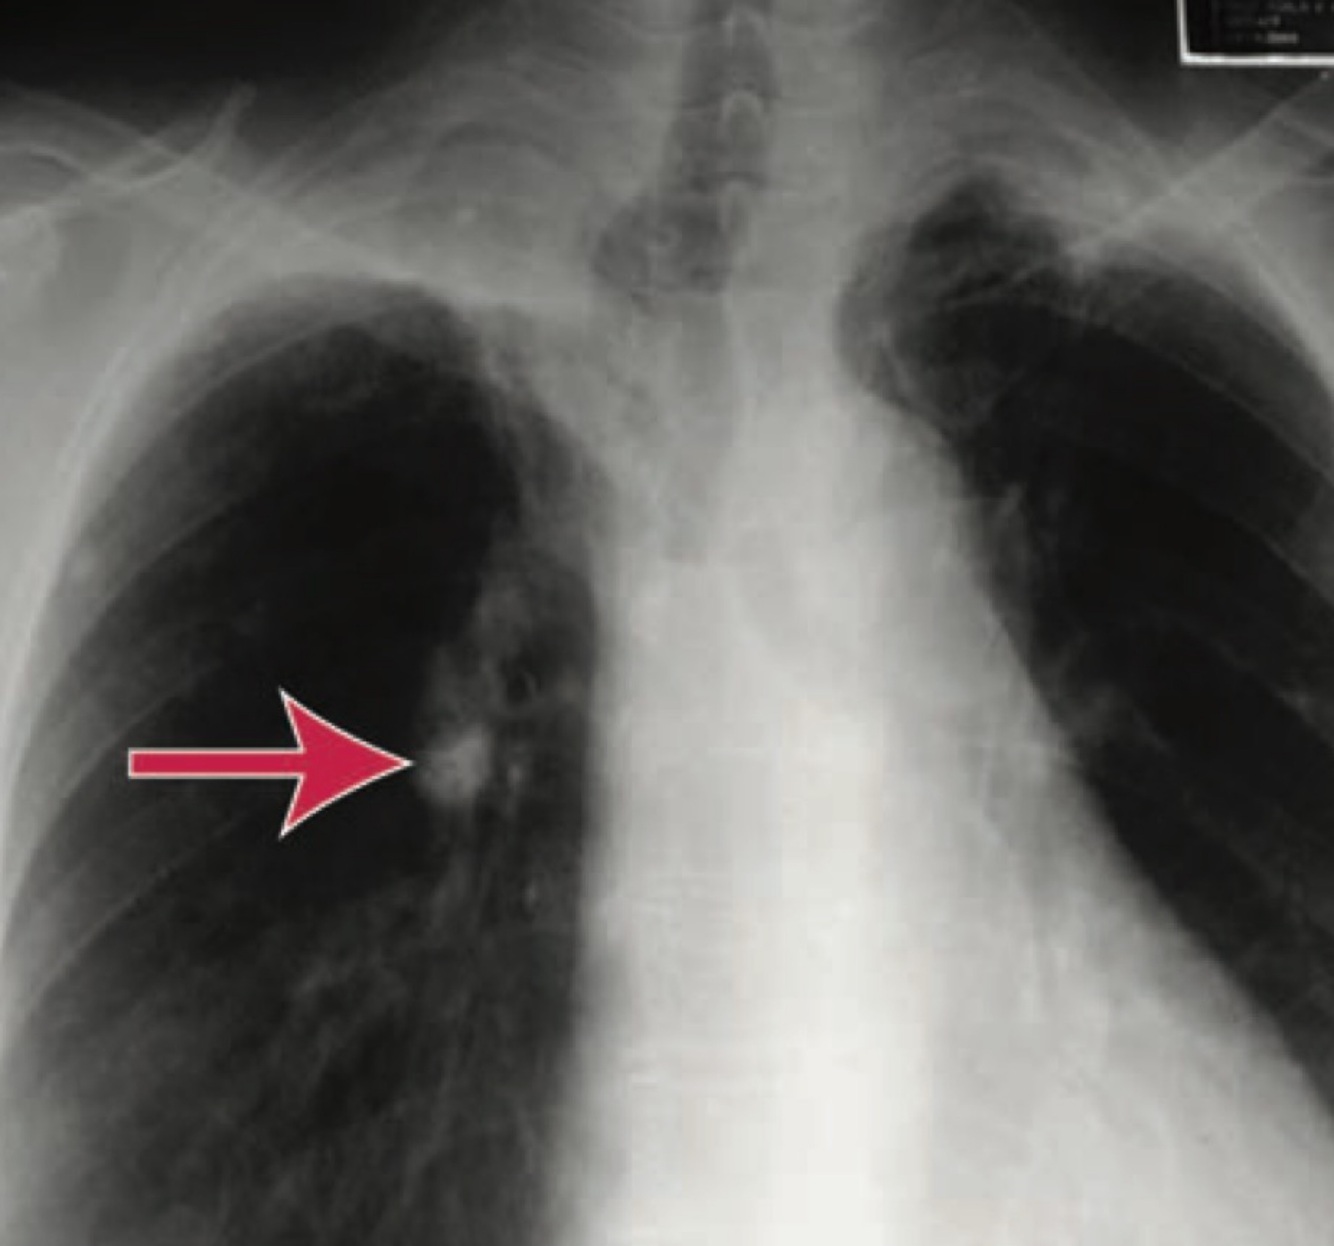

IDENTIFY

Primary Ghon complex (arrow)

is a tubercle, appearing as calcified hilar lymph nodes.